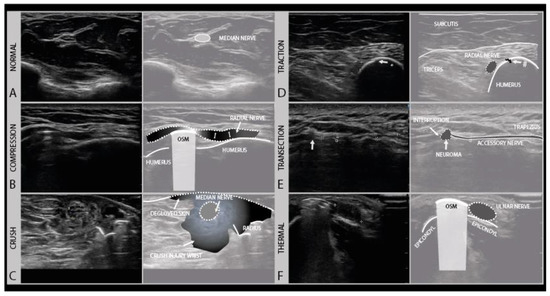

Figure 7.

Examples of different trauma types. The normal transverse aspect of a median nerve in the forearm (A). Local compression injury of the radial nerve by local osteosynthesis material (OSM). Focal enlargement of the nerve diameter proximal to the lesion site can be seen (B). Crush injury of the median nerve at the level of the forearm with surrounding crushed subcutaneous tissue and degloved skin (C). Traction injury of the radial nerve after humeral fracture (#). Swollen and hypoechoic aspect of the radial nerve (D). Iatrogenic transection injury of the accessory nerve after resection of a local lipoma. A stump neuroma can be seen at the site of nerve injury, with a loss of continuity. (E). Swollen and hypoechoic ulnar nerve after thermal injury (hot K-wire) at the level of the medial epicondyle with in situ osteosynthesis material (F).

Compression injuries can either be acute or chronic. Acute compression injury, such as a peri-operative ulnar compression neuropathy, typically presents with transient paresthesia, numbness and accompanying weakness that recover in weeks. Chronic compression, e.g., carpal tunnel syndrome, is often a progressively worsening condition that persists without proper intervention. Clinically, symptoms start with paresthesia and often also pain, and progress over time to hypesthesia and muscle weakness, depending on the extent of axonal damage [33]. In the case of nerve entrapment, a focal area of nerve enlargement can be seen just proximal to the site of compression. Ultrasound not only helps with localizing the compression site but could also help in identifying its cause. An example of such nerve entrapment, caused by osteosynthesis material in this patient, is shown in Figure 7B. In this case, the radial nerve shows the focal enlargement just proximal to the screw where it is compressed. In addition to a CSA increase, this caliber change can be appreciated quite well in the longitudinal images. When entrapment is severe or chronic, an associated loss of the internal fascicular architecture can be observed as well.

The initial therapy after traction injury is conservative and includes pain management, rehabilitative measures and a minimum follow up after 3 and 5 months. If conservative treatment fails, surgical exploration and reconstruction should be considered within 6 months [37,38]. Depending on the severity of the injury, the nerve will appear hypoechoic and swollen, with or without a disruption of the fascicular architecture. Figure 7D shows an example of a traction injury of the radial nerve, just proximal from a humerus fracture site. In the longitudinal images, the epineurium of the nerve can be seen to be intact.

Crush injuries occur from the traumatic compression of the nerve by blunt force, such as from the nerve and surrounding tissue being hit with a bat or ran over by car, getting caught in industrial machinery such as crushing rollers, or pinched between surgical clamps. Crush injuries can cause different degrees of nerve damage ranging all the way from neurapraxia to (partial) neurotmesis. Complete traumatic disruption with nerve transection (i.e., Sunderland grade 5) is rare, but the internal nerve structure can be badly damaged (i.e., Sunderland grade 4). Recovery follows the rules of the Sunderland grading system. Nerve ultrasound at the site of the injury will show a hypoechoic and enlarged nerve with more or less disrupted fascicle architecture and in the acute phase ecchymoses and edema of the surrounding tissues, as shown for example in Figure 7C.

4.4. Thermal Injury

4.5. Transection (“Sharp”) Injury

Complete nerve transection injuries are usually caused by “sharp” accidents, such a knife laceration, glass shard injury, bone drill or gunshot wound. Gunshot wounds, however, are complicated, as they can both damage the nerve directly, or damage the nerve with bone fragments from splintering upon impact, but can also cause severe traction/compression injury from the pressure waves that build up in the bullet trajectory or the subsequent compartment syndrome these pressure changes cause. After complete nerve transection (i.e., Sunderland grade 5, neurotmesis), the distal segment of the nerve will undergo Wallerian degeneration, and there is no chance of recovery across the gap as the proximal and distal nerve ends typically retract. In transection injuries, the nerve ultrasound can be used in the acute setting to reveal the discontinuation of the nerve, often best appreciated in the longitudinal direction. The hallmark is an interruption of the epineurial sheath and the fascicles. In transverse images, the nerve and fascicles in the stumps appear enlarged and hypoechoic, and over time this architecture will become more disrupted as stump neuromas develop (Figure 7E). Surgical treatment, with neurolysis and repair or grafting is the only option for nerve recovery; if this is not possible, tendon transfers and joint stabilization by splinting or arthrodesis should be considered.